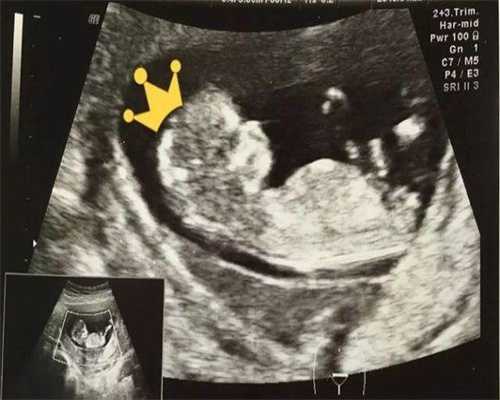

第五天的1枚6AB囊胚属于优质囊胚,移植成功率可以达到50%-60%左右。该囊胚处于孵出期,其囊胚内细胞数目多而且排列紧密,滋养层细胞的上皮细胞层由不多的细胞组成,结构松散。不管是质量还是还是移植后的成功率都是很高的,不过高成功率并不代表百分百的成功。囊胚的移植成功率还会受患者年龄、子宫内部环境、医生技术等因素影响。

在试管婴儿过程中养成的囊胚质量是影响囊胚移植成功率的重要因素,而6ab囊胚在临床上是属于等级比较高的囊胚,移植成功是比较高的。但是由于各种因素的影响,不同患者进行囊胚移植的成功率就有所差异。下面是移植一枚第5天的6AB囊胚的成功率分析:

6AB囊胚的质量不错,移植成功率比较高,如果患者身体支持的话,一般移植一次就可以成功,而患者身体素质不好,可能需要移植多次才能成功。

根据试管临床数据来看,囊胚移植成功率会高于3天的胚胎,但是需要注意的是囊胚移植也不保证一定能成功,囊胚移植后到底能否成功与患者的身体情况也有着密切关系。

6天的6aa的冻囊胚移植成功率一般在50%-60%之间,6aa囊胚是指囊胚处于第6期,且细胞团内的细胞数目多,排列紧密,且滋养层细胞的上皮细胞层由较多细胞组成,结构致密,属于最好的囊胚。原则上来说,6aa的囊胚其质量时最优秀的,因此移植的成功率也是要高于其他等级囊胚的,但移植的成功率并不取决于囊胚的等级,还要综合其他条件一起考虑。